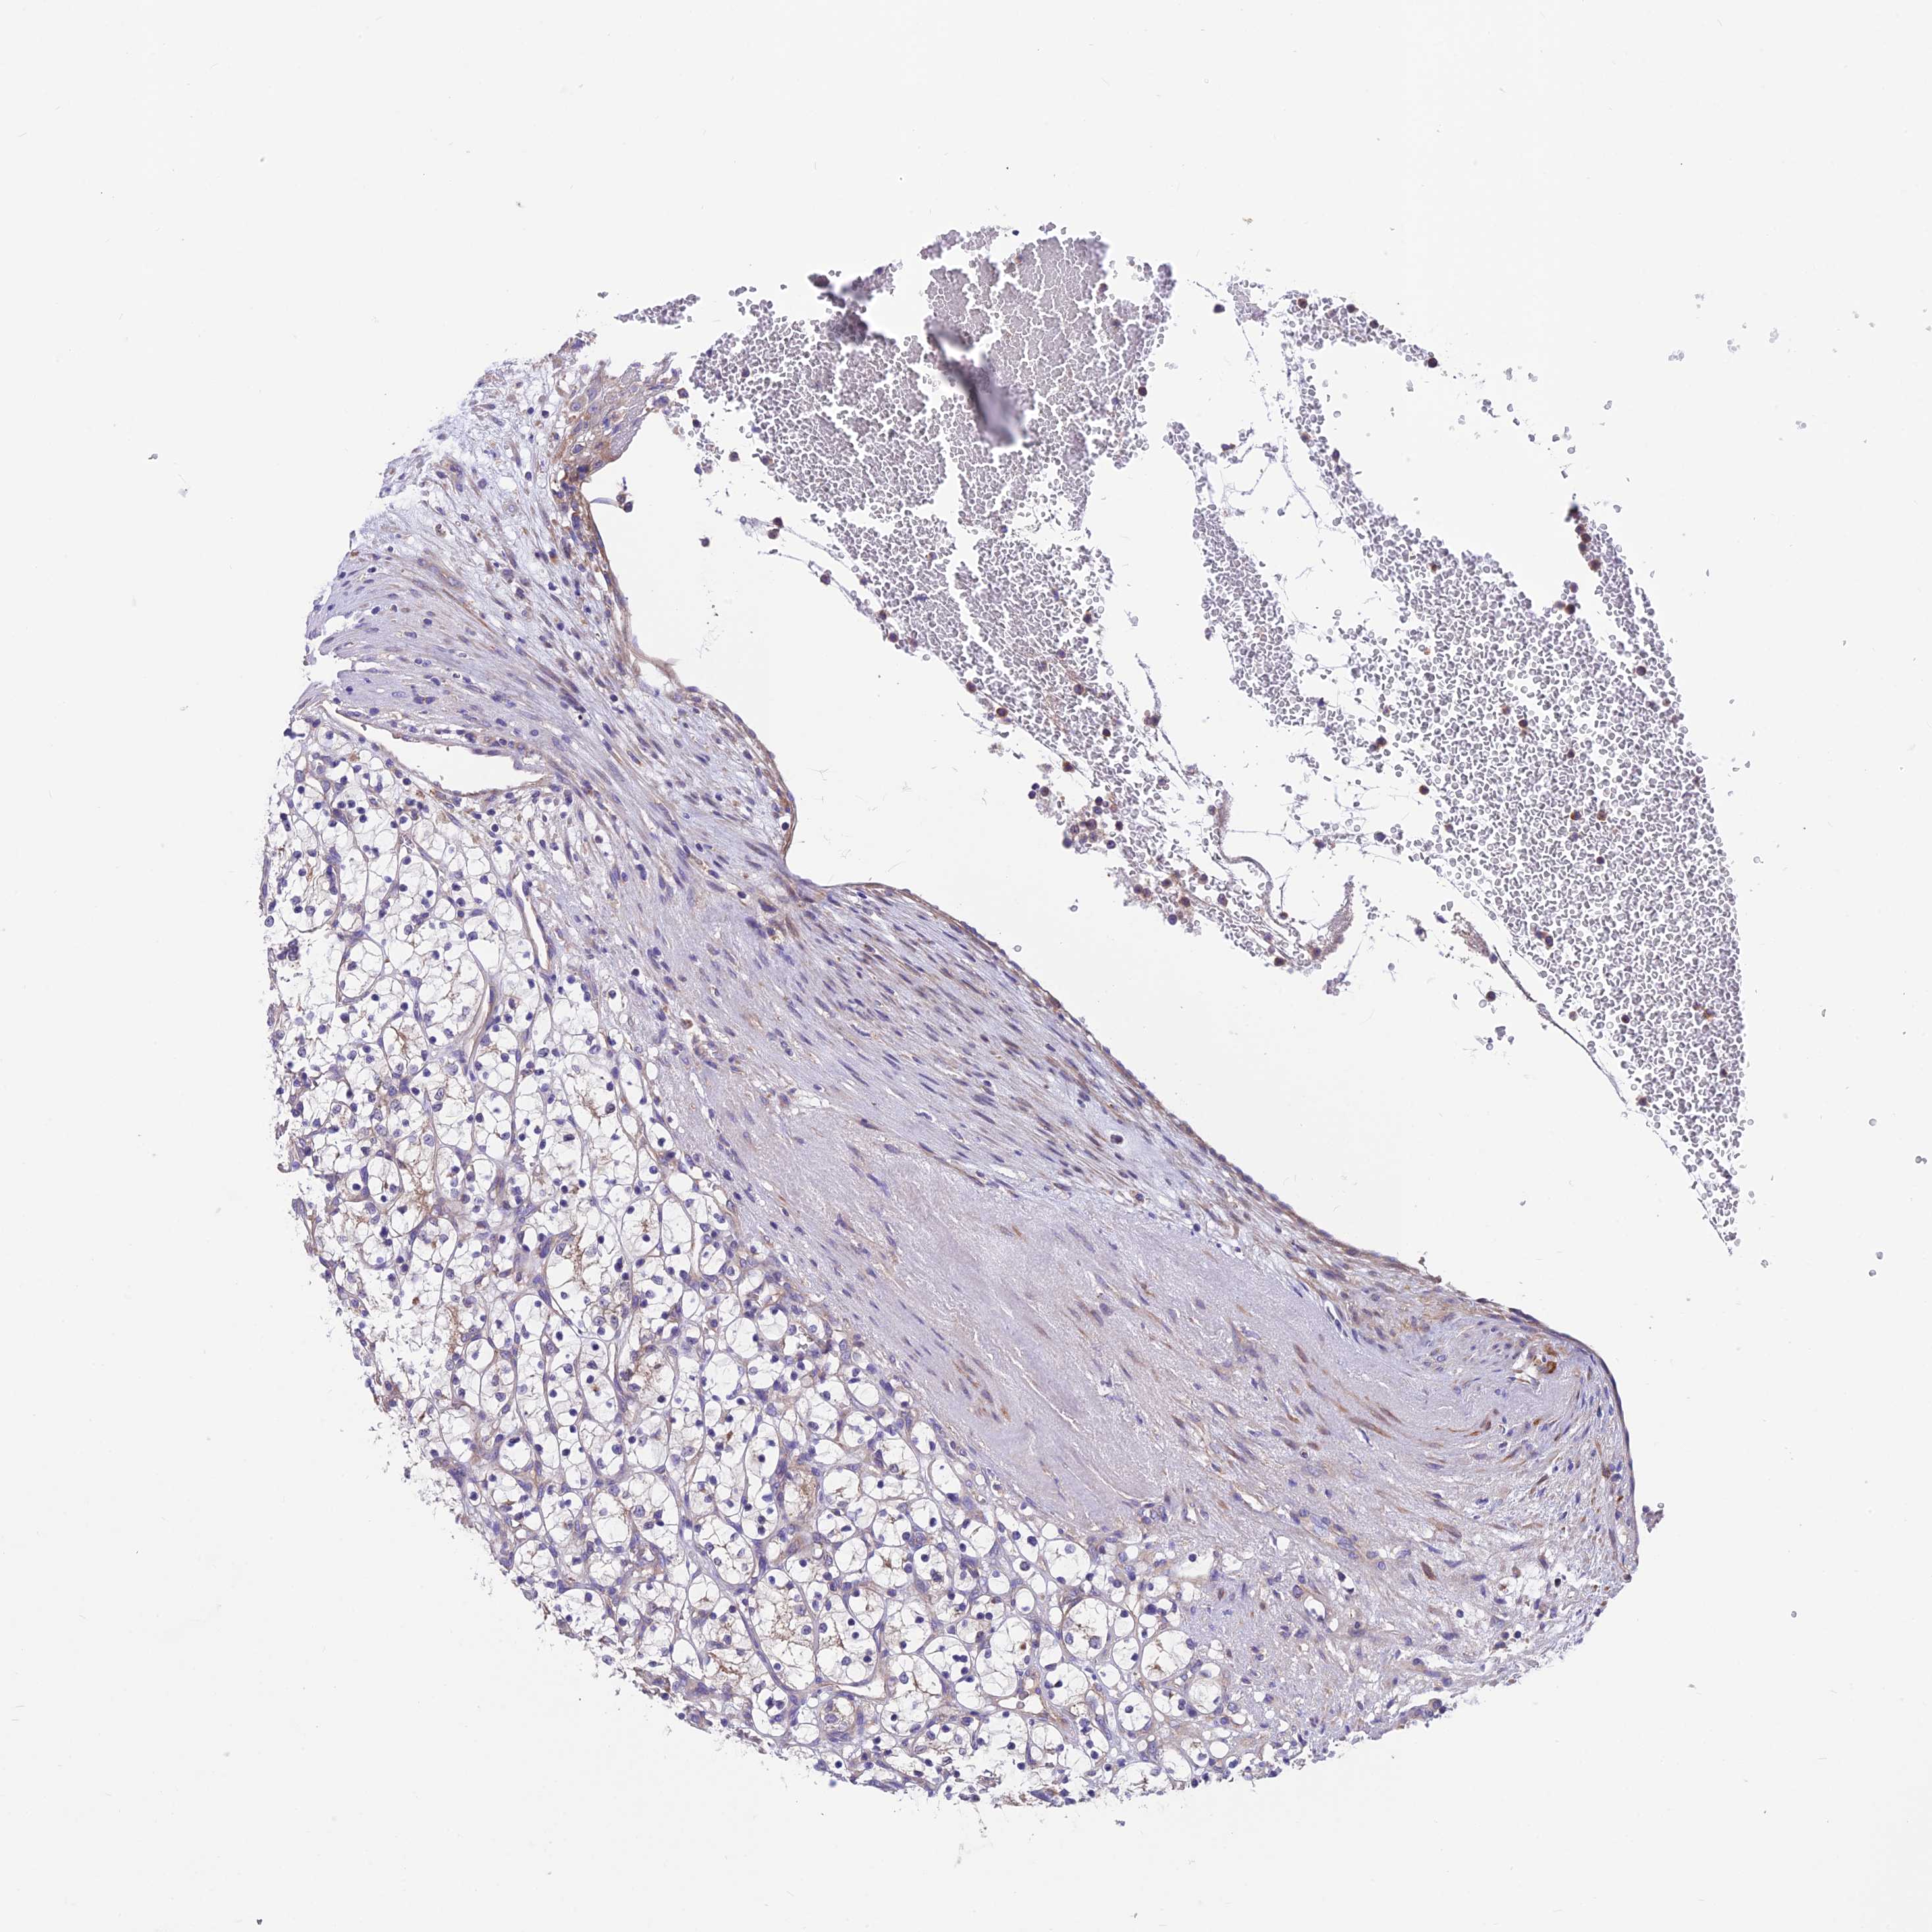

KIDNEY RENAL CLEAR CELL CARCINOMA (VALIDATION) - Interactive survival scatter ploti

The Survival Scatter plot shows the clinical status (i.e. dead or alive) for all individuals in the patient cohort, based on the same data that underlies the corresponding Kaplan-Meier plots. Patients that are alive at last time for follow-up are shown in blue and patients who have died during the study are shown in red.

The x-axis shows the expression levels (FPKM) of the investigated gene in the tumor tissue at the time of diagnosis. The y-axis shows the follow-up time after diagnosis (years). Both axes are complimented with kernel density curves demonstrating the data density over the axes. The top density plot shows the expression levels (FPKM) distribution among dead (red) and alive patients (blue). The right density plot shows the data density of the survived years of dead patients with high and low expression levels respectively, stratified using the cutoff indicated by the vertical dashed line through the Survival Scatter plot. This cutoff is automatically defined based on the FPKM cutoff that minimizes the p-score. The cutoff can be changed by dragging the vertical line or by entering a cutoff value in the square labeled "Current cut-off".

Under the Survival Scatter plot the p-score landscape (black curve; left axis) is shown together with dead median separation (red curve; right axis). Dead median separation is the difference in median mRNA expression between patients who have died with high and low expression, respectively. It is calculated as follows: median FPKM expression of dead patients with high expression - median FPKM expression of dead patients with low expression. This is intended to aid the user in visually exploring custom cutoffs and the associated p-scores and dead median separation.

Individual patient data is displayed and can be filtered by clicking on one or more of the category buttons on the top of the page. Categories describing expression level and patient information include: high, low, alive, dead, female, male and tumor stages. The scale of the x-axis can be toggled between linear and log-scale by clicking on the "x log" button. Mouse-over function shows TCGA ID, patient information and mRNA expression (FPKM) for each patient.

& Survival analysisi

Kaplan-Meier plots summarize results from analysis of correlation between mRNA expression level and patient survival. Patients were divided based on level of expression into one of the two groups "low" (under cut off) or "high" (over cut off). X-axis shows time for survival (years) and y-axis shows the probability of survival, where 1.0 corresponds to 100 percent.

VPS16 is not prognostic in Kidney Renal Clear Cell Carcinoma (validation)

Best expression cut offi

Based on the FPKM value of each gene, patients were classified into two groups and association between prognosis (survival) and gene expression (FPKM) was examined. The best expression cut-off refers the FPKM value that yields maximal difference with regard to survival between the two groups at the lowest log-rank P-value. Best expression cut-off was selected based on survival analysis .

When clicking on this number, the vertical dashed line indicating cut-off, the interactive survival plot, and the Kaplan-Meier curve will be adjusted to show results based on the best expression cut-off.

: 24.05

Median expressioni

Median expression refers to the median FPKM value calculated based on the gene expression (FPKM) data from all patients in this dataset. When clicking on this number, the vertical dashed line indicating cut-off, the interactive survival plot, and the Kaplan-Meier curve will be adjusted to show results based on the median expression.

: N/A

Median follow up timei

Median follow up time refers to the median time (years) after diagnosis with this type of cancer, based on clinical data from all patients in this dataset.

P scorei

Log-rank P value for Kaplan-Meier plot showing results from analysis of correlation between mRNA expression level and patient survival.

N/A

5-year survival highi

5-year survival for patients with higher expression than the expression cutoff.

For melanoma and glioma, 3-year survival is shown.

5-year survival lowi

5-year survival for patients with lower expression than the expression cutoff.

TCGA RNA samplesi

RNA-seq data is reported as average FPKM (number Fragments Per Kilobase of exon per Million reads), generated by the The Cancer Genome Atlas (TCGA) .

Normal distribution across the dataset is visualized with box plots, shown as median and 25th and 75th percentiles. Points are displayed as outliers if they are above or below 1.5 times the interquartile range. FPKM values of the individual samples are presented next to the box plot.

Average pTPM 21.1

Number of samples 100